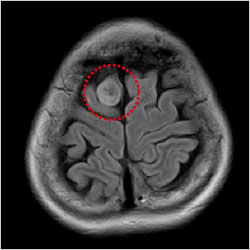

脳腫瘍(髄膜腫)

脳梗塞、脳動脈瘤、脳腫瘍など脳の病気を早期に発見することを目的とします。